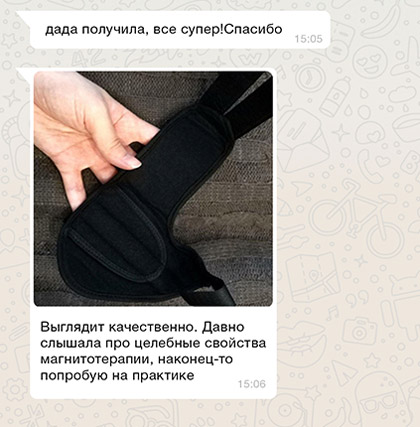

С целью устранения Hallus valgus (бурсита) и негативных симптомов, сопровождающих деформацию ступней, успешно применяется магнитотерапия. Магнитотерапия – уникальный метод физиотерапевтического лечения с помощью воздействия на организм постоянным, переменным или бегущим магнитным полем. Процедура является безопасной и не вызывает болезненных ощущений.

Чтобы купировать воспалительный процесс, достаточно использовать магнитную шину FootRelax ежедневно в течение 3-5 часов. Это способствует не только выравниванию фаланг пальцев и уменьшению деформации, но также благодаря воздействию магнитов происходит стимуляция нервных окончаний, повышается тонус тканей, улучшается кровообращение. FootRelax фиксирует большой палец в нужном положении, снижает нагрузку на ступни, купирует боль, облегчает ходьбу и возвращает здоровья ступням.